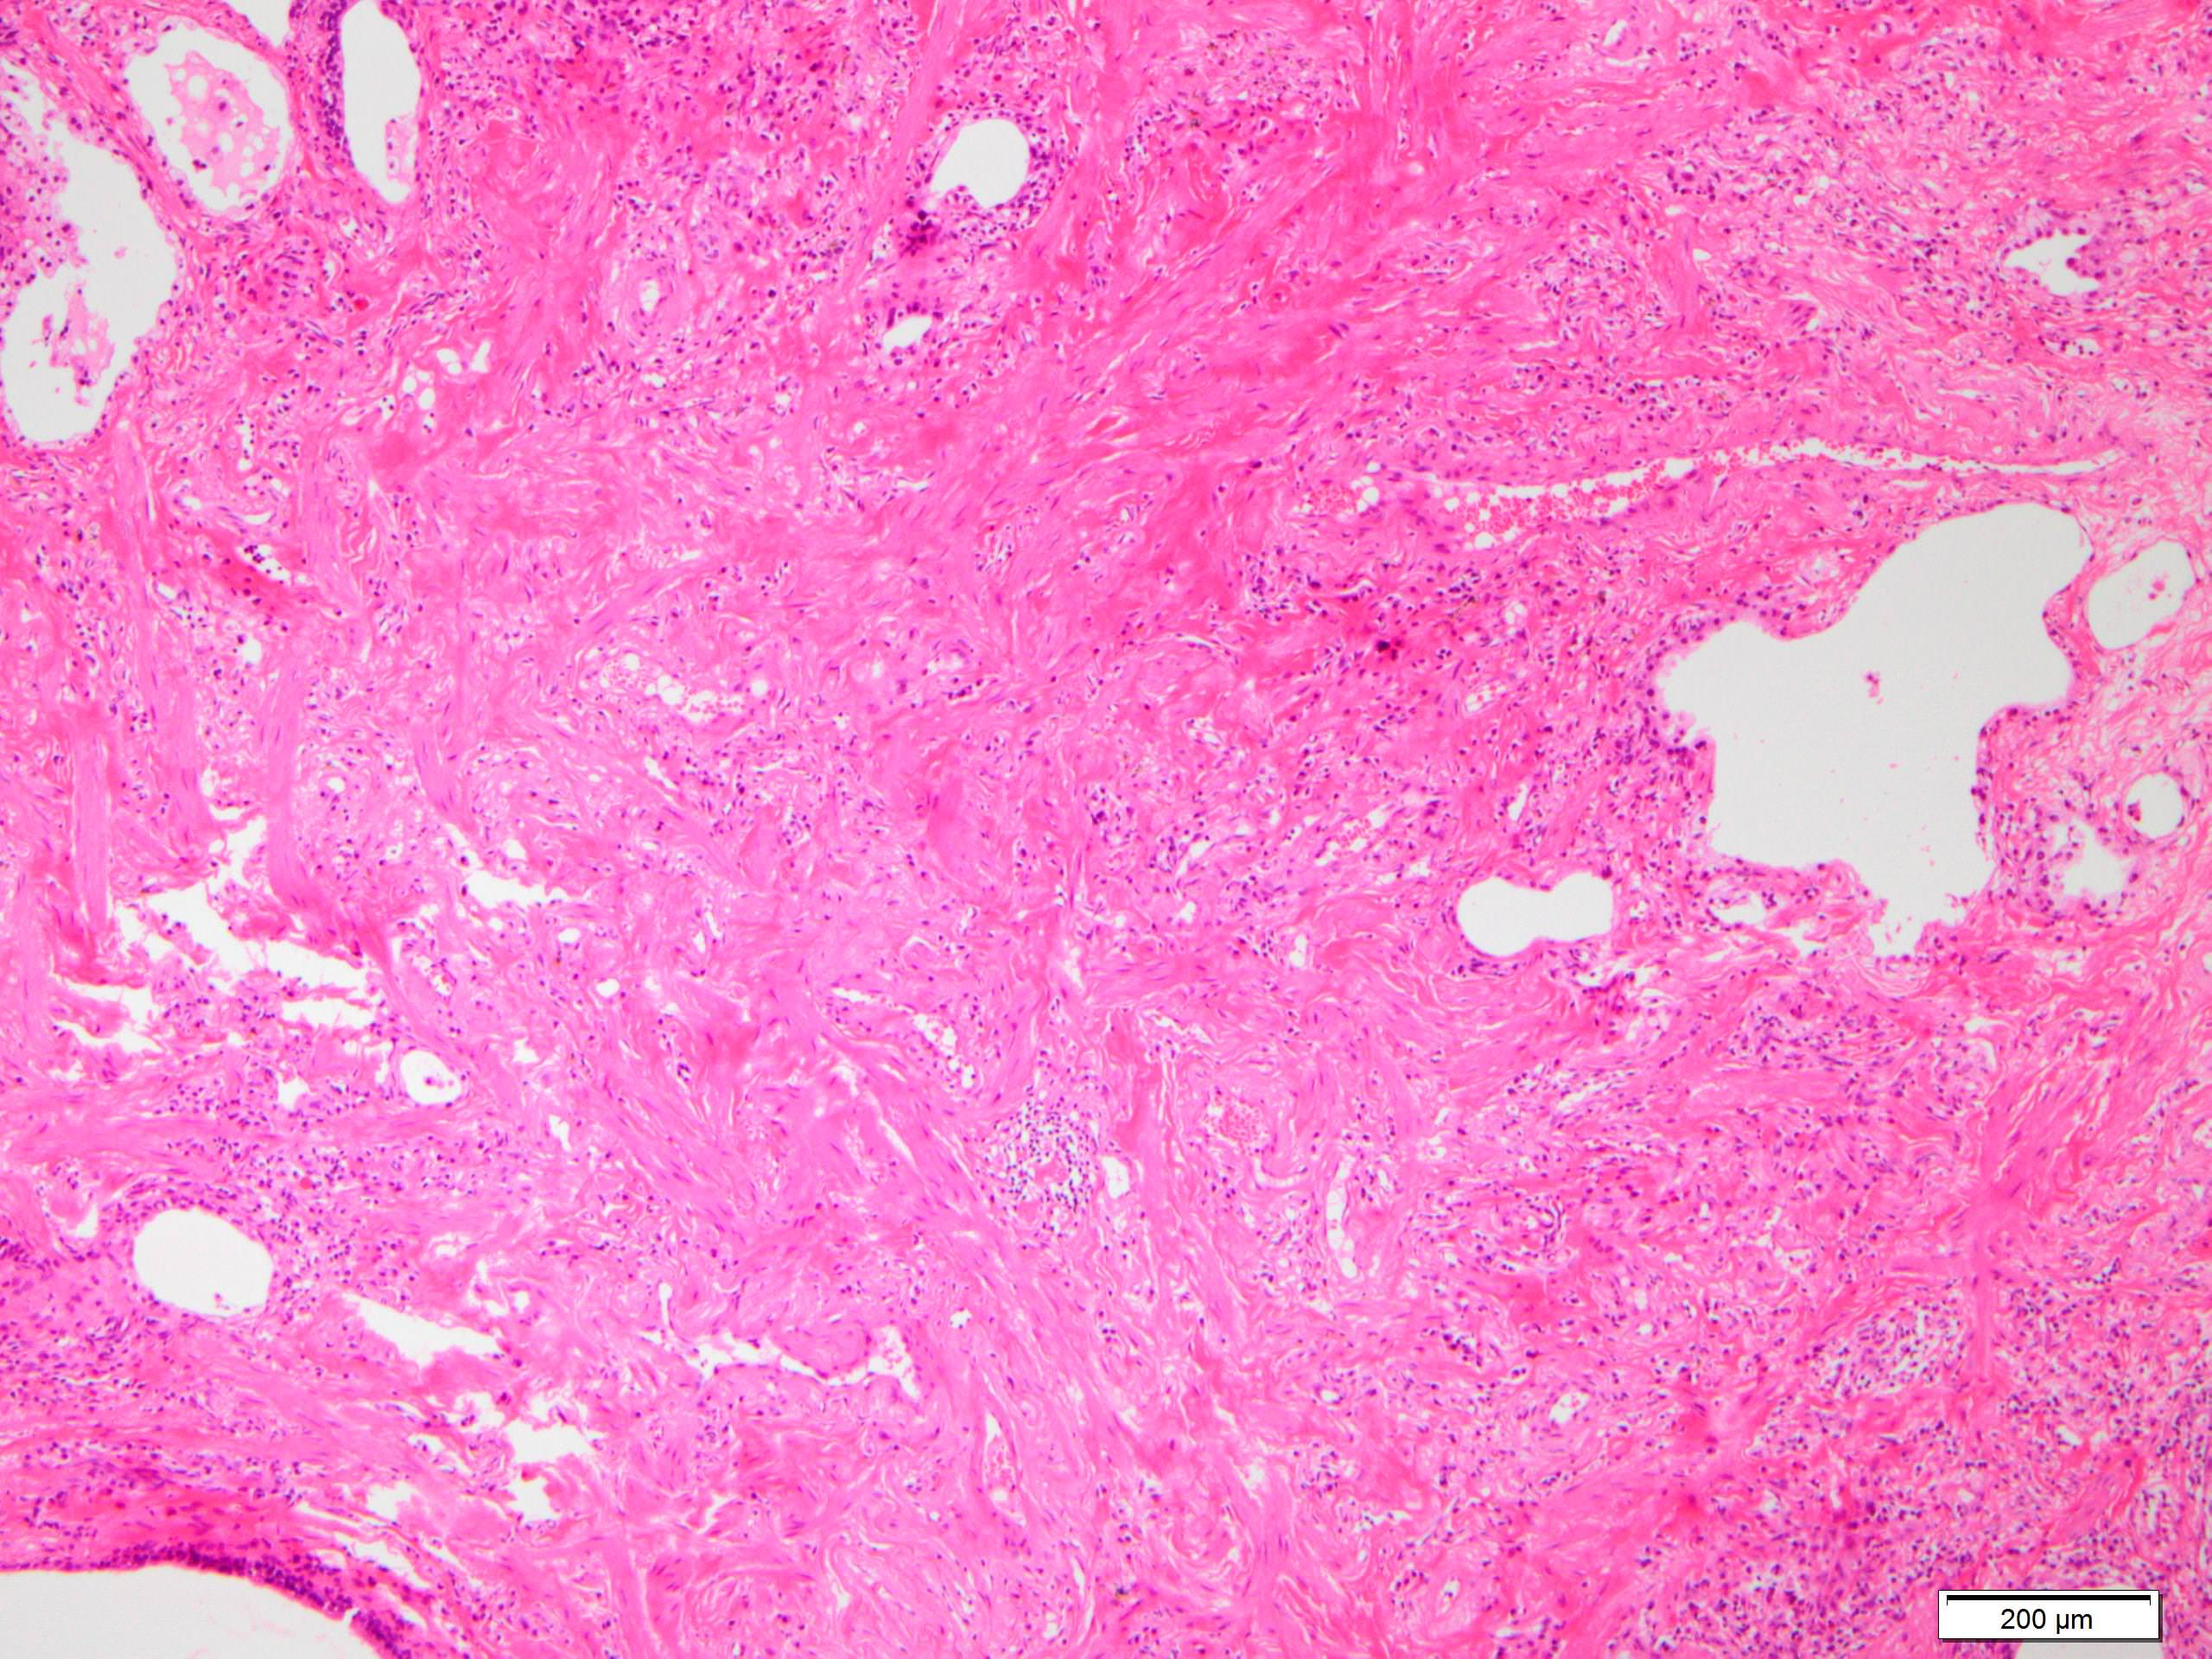

Microscopic (histologic) description

- Since there are few specific findings for NSIP pattern, it is essential to exclude other lung diseases on histology (Am J Respir Crit Care Med 2008;177:1338)

- Characteristic findings of NSIP pattern

- Diffuse and uniform inflammation ("temporal homogeneity") on low power of alveolar wall, bronchovascular bundles and pleura

- Cellular or fibrotic change

- Lymphocytic or plasmacytic infiltration

- Loose fibrosis

- Lung architecture is frequently preserved

- "Cellular NSIP" or "fibrotic NSIP" can be stated specifically in pathologist report

- Diffuse and uniform inflammation ("temporal homogeneity") on low power of alveolar wall, bronchovascular bundles and pleura

Microscopic (histologic) images

Scroll to see all images.

Contributed by Akira Yoshikawa, M.D.

Images hosted on other servers:

Contributed by Akira Yoshikawa, M.D.

Images hosted on other servers: